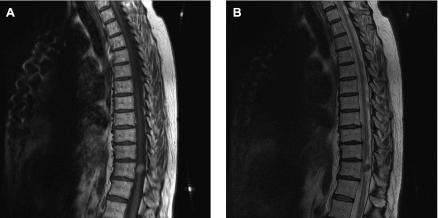

We present a case of an intramedullary melanotic schwannoma (IMS) of the thoracic spinal cord. To our knowledge, this is the seventh reported case of an IMS of the central nervous system. Schwannomas are benign nerve sheath tumors of neural crest origin composed entirely of well differentiated Schwann cells that typically occur in peripheral nerves. Both the intramedullary location and the melanotic component of the reported lesion make it exceedingly rare. We will present our case, theories as to the origin of these tumors, clues in radiographic identification, and current clinical follow-up recommendations.

我们报告一例胸段脊髓髓内黑色素性神经鞘瘤(IMS)。据我们所知,这是中枢神经系统IMS报告的第七例。神经鞘瘤是起源于神经嵴的良性神经鞘肿瘤,完全由分化良好的施万细胞组成,通常发生于周围神经。所报告病变的髓内位置和黑色素成分使其极为罕见。我们将展示我们的病例、这些肿瘤的起源理论、影像学识别线索以及当前的临床随访建议。